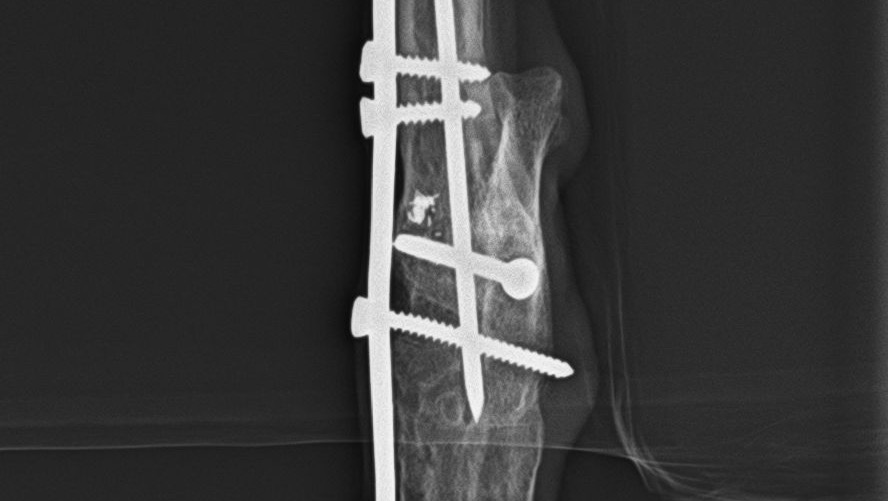

Hi, my name is Adel, and this is my beloved dog, Minka. We moved to Vancouver 1,5 years ago. She’s been with me for 7 amazing years, but her life has been full of hardship. Minka was found when she was about 1 year old, after being abused and beaten, someone deliberately broke her leg, and she had an emergency operation at the shelter. Despite the orthopedic problems, I decided to adopt her, as I fell in love with her.

Over the years, she has undergone six surgeries by my side, and I have spent every penny I had to make sure she received the medical care she needed. Unfortunately, because of these surgeries, her leg became extremely tight and shortened, causing chronic pain and affecting her posture. She struggles to stand evenly, and watching her live with this constant discomfort breaks my heart.

Her vets have recommended one last specialized surgery that could finally allow her to put her leg down properly, improve her posture, and relieve much of her chronic pain. Unfortunately, I cannot afford this surgery on my own, and I’m asking for help to give Minka the comfort and mobility she deserves. She would be operated in Hungary and it would cost 1100 CAD.